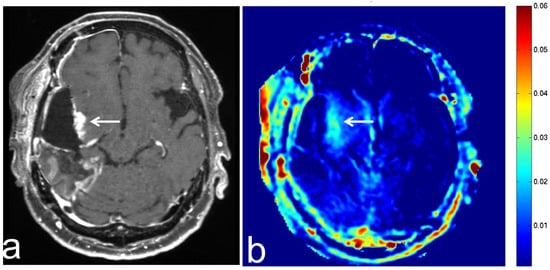

5.3. Glioblastoma